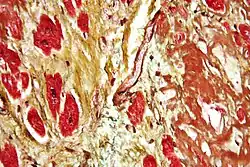

Одной из наиболее опасных форм течения ИБС и одной из основных причин смерти является инфаркт миокарда (ИМ) – некроз (гибель) участка миокарда вследствие резкого ухудшения коронарного кровотока, в большинстве случаев сопровождаемый развитием характерной клинической картины, ЭКГ - изменениями и динамикой активности маркеров некроза миокарда в крови. ИМ классифицируют по различным критериям: размер, локализация, сроки от начала развития и проч.[6]

Миокардиты – это совокупность клинических и морфологических изменений тканей сердца (кардиомиоциты, клетки проводящей системы, соединительнотканной структуры и т.д.) в случаях, когда доказано или обоснованно предполагается наличие воспалительных изменений миокарда инфекционной или аутоиммунной природы. ВОЗ и Международное общество кардиологов (ISFC) определили миокардит как воспалительное заболевание мышцы сердца, диагностированное по гистологическим, иммунологическим или иммуногистохимическим критериям. Воспалительный процесс может быть острым или хроническим и является следствием воздействия различных этиологических факторов, поражающих миокард непосредственно и/или опосредованно через аллергические иммунные механизмы[12].